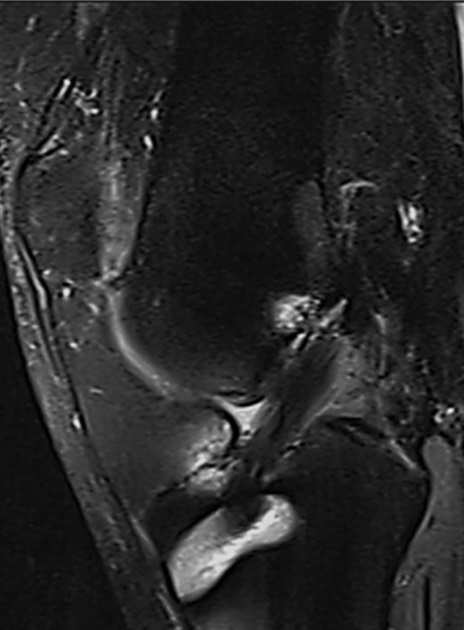

Todos los pacientes fueron evaluados con RNM a los 6 meses para consignar la intensidad de la señal del injerto (Fig. 4).

Figura 4. Control con RNM al sexto mes del postoperatorio para evaluar señal del injerto y determinar el grado de madurez.

En relación a la maduración/ligamentización del injerto y su visualización a través de imágenes de RNM, Figueroa y cols. realizaron un estudio secuencial retrospectivo de pacientes sometidos a RLCA, comparando un protocolo de injerto sin preinmersión en vancomicina con otro de injerto con preinmersión. Se obtuvieron las puntuaciones de Lysholm y del IKDC tras un seguimiento mínimo de 24 meses. Entre los 6 y los 12 meses de seguimiento se efectuó una resonancia magnética (RNM) para evaluar la consolidación e integración del injerto. Los autores concluyeron que el prelavado con vancomicina de los injertos de isquiotibiales aumentó el número de injertos hiperintensos e isointensos en la RNM. En contraste, se observaron más injertos hipointensos cuando no se utilizó vancomicina, lo que sugiere la presencia de injertos más maduros en ese grupo. Así, el remojo previo con vancomicina de autoinjertos de isquiotibiales en la RLCA se asocia con una mayor señal del injerto en la RNM, aunque sin influir en el resultado clínico.25